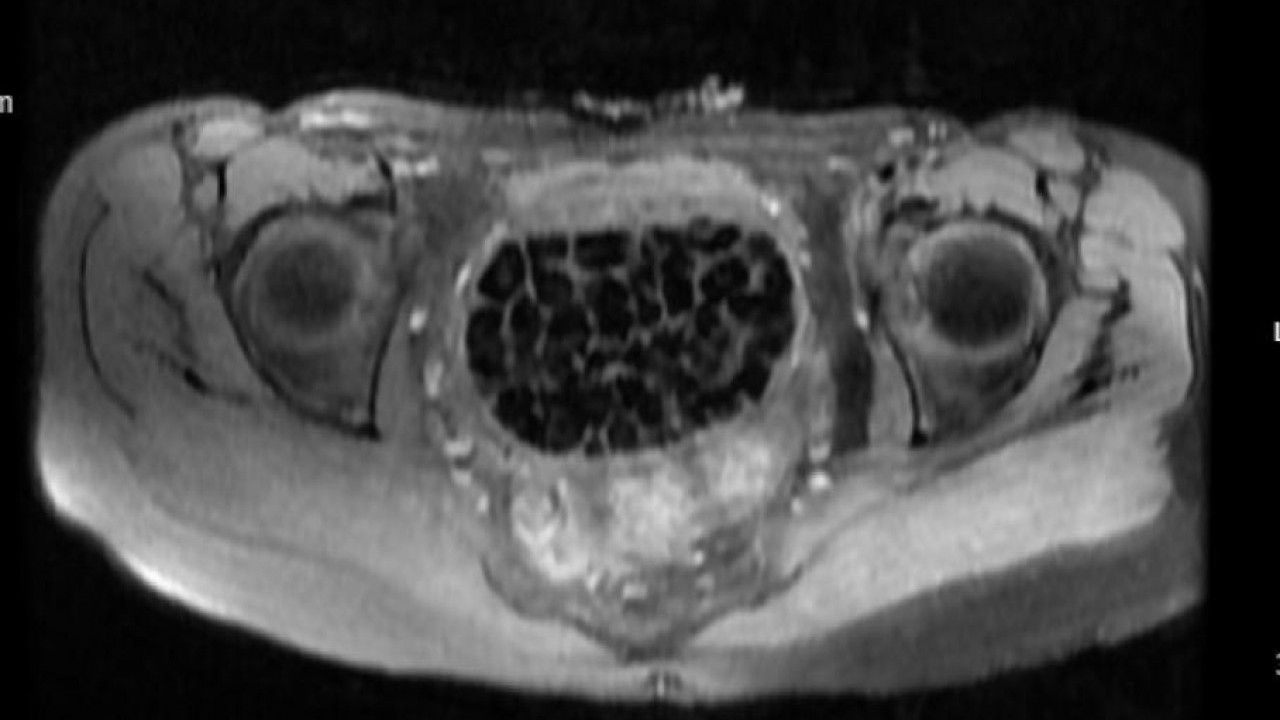

287 taş hem doktorları hem hasta ve ailesini şok etti Genç kızın ameliyat işlemleri başlatılırken 11 Eylül’deki operasyon sırasında doktorlar da şaşkınlık yaşadı. Öztürk’ün vücudundan 287 adet çeşitli ölçülerde taş çıkarılırken üroloji ve jinekolojik onkoloji ekibi operasyonu başarıyla tamamladı. Taşların sayısını duyan genç kız ve ailesi şok olurken operasyonun ardından karın ağrıları dinen Öztürk, rahat bir nefes aldı. Tedavisi sonrası taburcu edilen genç kız yaşadıklarını anlatırken, operasyonu gerçekleştiren Üroloji Uzmanı Doç. Dr. Erkan Erkan ile Jinekolojik Onkoloji Uzmanı Op. Dr. Emin Erhan Dönmez de nadir olduğunu ifade ettikleri vakaları hakkında bilgi verdi, önemli uyarılarda bulundu. Öte yandan, genç kızın vücudundaki 287 taşın tetkiklerdeki görüntüsü dikkat çekerken taşlar üzerine de incelemeler yapılacak.

"287 adet taş çıkardık, literatürde çok nadir görülen bir olay" Hastasının durumuna yönelik konuşan Üroloji Uzmanı Doç. Dr. Erkan Erkan, "Hastamızın 2004 yılında doğduğunu ardından doğar doğmaz ekstrofi vezika dediğimiz 50 binde bir görülen bir anomaliden dolayı art arda ameliyatlar geçirdiğini öğrendik. 10 yaşında yine bir ameliyat geçirmişti, gerekli görüntüleme ve tetkiklerimizi yaptırdık. Normalde mesanesinin olması gereken yerin hemen arka kısmında taşlarla dolu bir kese olduğunu gördük, bunun üzerine ek görüntülemeler; MR çektirdik. Hastamız çelişkili açıklamalar almıştı, kendi radyolojik kliniğimiz ve edindiğimiz konsültasyonlarda taşların mesanede değil vajinal boşlukta oluştuğunu düşündük, bir planlama yaptık. Kadın doğum hocamızın da çabasıyla taşları tamamen temizledik ardından ileride normal bir hayat sürmesi bakımından oraya plastik cerrahi yaptık. 287 adet taş çıkardık, pratikte gerçekten görünce çok şaşırdık çünkü bu aynı zamanda literatürde çok nadir görülen bir olay. Biz ameliyata hazırlanırken de teorik olarak biraz araştırdık. Literatürde gördüğümüz kadarıyla buna benzer bu tanıma uyan bir vaka vardı. Literatürde sanırım yayınlanmış 2’nci vaka olacak. Farkındalık çok önemli, bilinçli bir hastamız vardı. Doğumsal anomaliyle doğan çocuklarımızda ileride bunlara bağlı bazı sıkıntılar çıkabileceğinin öngörülmesi lazım. İlgili tedavilerini alsalar bile düzenli takiplere gelmeleri gerekiyor. İleride eğer dikkat etmezse ki zannetmiyorum, tekrarlayabilir. Bu rahatsızlık ekstrofi vezikal epispadias durumu çok nadir bir durum" dedi.

"Tüm vajenin taşlarla dolu olduğunu gördük" Genç kızın uzun süredir devam eden karın ağrısı olduğunu söyleyerek sözlerine başlayan Jinekolojik Onkoloji Uzmanı Op. Dr. Emin Erhan Dönmez, "Mesane taşları olduğu düşünülerek daha büyük bir hastaneye refere edilmiş. Aramızda mini bir konsey yaparak muayene ettik. Vajen bir hazne görevi görerek orada durağan bir idrar, uzun süre beklediği için idrar içindeki minerallerde çökerek taşlar oluşmuş. Mesanedeki idrarın vajene akmış olabileceği ve vajende göllenen idrar nedeniyle taşların burada oluşacağını düşündük, ameliyatımızı planladık. Ameliyata tanı amaçlı girmiştik, sistoskopi (Mesane gibi idrar yollarını kapsayan kısımlardaki rahatsızlıkların teşhis ve tedavisinde kullanılan endoskopik bir yöntem) dediğimiz ameliyatı Erkan Hocam ile birlikte gerçekleştirdik. Önce mesaneyi bir görüntüledik, mesane tabanına yaklaşık 2-3 cm’lik bir alandan vajene fistülize olduğunu gördük. Mesaneden vajene geçtiğimiz esnada tüm vajenin taşlarla dolu olduğunu gördük.

Tanı amacıyla girdiğimiz ameliyatta her şey de olağan gittiği için tedaviye geçtik. Taşların çıkabileceği kadar bir genişlik sağladık. Daha sonra yaklaşık en büyüğü 2,5 cm boyutlarında olan, irili ufaklı 287 tane taşı ameliyat esnasında çıkarmış olduk. Taşların tekrarlamaması için idrarın göllenmemesi, en azından dışarıya rahatça boşalabilmesi için vajinal rekonstrüksiyonu sağladık. Ameliyatta da herhangi bir problem yaşamadık. Literatürü Erkan Hocam ile birlikte değerlendirmiştik. Primer olarak vajende birikmiş olan bu kadar çok sayıda taşla ilgili bir makale görmedik, rastlamadık" dedi.